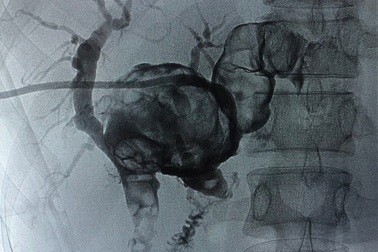

Đau bụng đi khám, người phụ nữ phát hiện sỏi đúc khuôn đầy trong ganĐi khám vì đau bụng, gầy sút cân, chị Vy (30 tuổi, Nghệ An) phát hiện sỏi đúc khuôn toàn bộ đường mật trong gan hai bên. Viên sỏi có kích thước to nhất lên đến 5cm, trong khi bình thường chỉ 1-2cm.